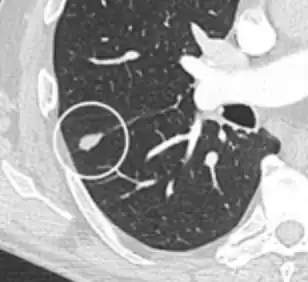

FDG-PET study of a 71-year-old woman with a solitary pulmonary nodule (thin arrow) in the left lower lobe near the heart. The scan also revealed abnormal increased activity at the gastro-esophageal junction (thick arrow). The final diagnosis was non-Hodgkin lymphoma at both sites.

If there is an intermediate risk of malignancy, further imaging with positron emission tomography (PET scan) is appropriate (if available). It can be done simultaneously as a CT scan in the form of PET-CT. Around 95% of patients with a malignant nodule will have an abnormal PET scan, while around 78% of patients with a benign nodule will look normal on PET (this is the test sensitivity and specificity).[15] Thus, an abnormal PET scan will reliably pick up cancer, but several other types of nodules (inflammatory or infectious, for example) will also show up on a PET scan. If the nodule has a diameter of less than one centimeter, PET scans are often avoided because of an increased risk of falsely normal results.[15][16][17] Cancerous lesions usually have a high metabolism on PET, as demonstrated by their high uptake of FDG (a radioactive sugar).